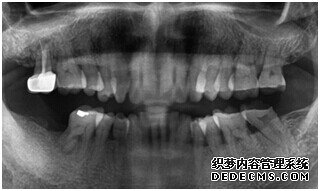

刘女士牙齿拍片初步检查

由CT片检查来看,刘女士口腔健康环境还是很好的,牙槽骨也适合种植牙的条件,而且由我们最后一颗牙是非常重要的,经过专家的建议和详细解释了原因之后,刘女士选择了美国百康种植牙。